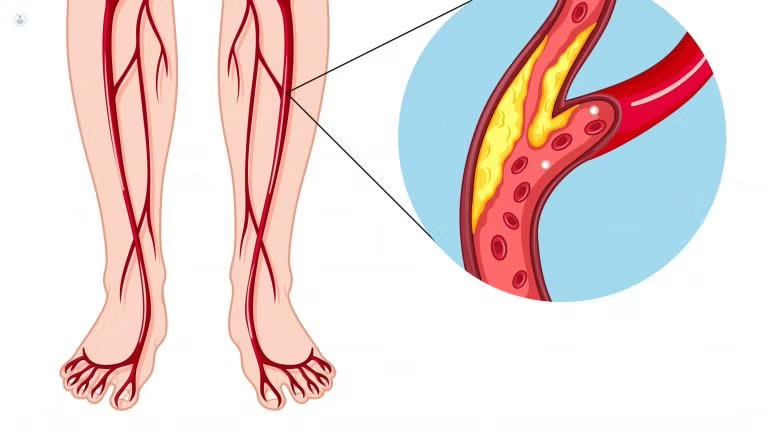

Las várices son venas dilatadas y tortuosas que aparecen principalmente en las piernas debido a una alteración en la circulación sanguínea. No solo representan un problema estético, sino que también pueden provocar dolor, cansancio, hinchazón y complicaciones venosas si no se tratan a tiempo.

Síntomas de las várices 👀

- Dolor o pesadez en las piernas.

- Hinchazón en tobillos y pies.

- Calambres nocturnos.

- Picazón, ardor o sensación de calor en la zona.

- Aparición de venas visibles, azuladas o moradas.